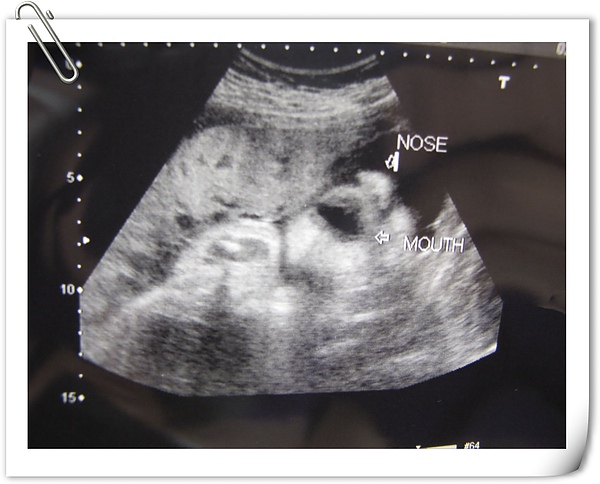

我問超音波師說鼻子算大嗎??

超音波師回答我:還好

這......我該如何跟米拔交待呀~~~~

這張是小嘴有張開喝羊水的樣子~~